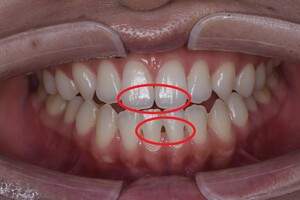

プロフェショナルクリーニング(PMTC)

治療前

治療後

| 年齢 | 26歳・女性 |

|---|---|

| 主訴 | 主訴:着色除去 治療部位:全顎 |

| 治療内容 | PMTC(自費診療) |

| 治療期間 | 30分 |

| 費用 | 5,500円 (2023年5月現在) |

| リスク・副作用 | ・生活習慣(喫煙・コーヒーなど)により再度着色することがあります。 ・PMTCは歯を白くするものではなく着色・バイオフィルムの除去を目的としています。 ・保険適用外の施術です。 |

| 治療方針 | プロフェショナルクリーニング(PMTC)後ホワイトニングを行う予定です。 |

| 特記事項 | 右下3番、2番の間に着色が目立ち、歯ブラシの動かし方の確認を行うとストロークが大きく、着色部位に歯ブラシが当たっていませんでした。歯ブラシが歯面に当たる角度を確認し、細かく振動を送るように動かすよう指導しました。一緒にステイン除去効果のある歯磨剤のおすすめを行いました。 |

| 担当者所見 | 右下3番、2番の間の着色が気になると来院されPMTCを行いました。喫煙の習慣はなく日常的にコーヒーを飲んでいるとのことでした。クリーニング後は歯がツルツルになったと喜んでくださいました。 |